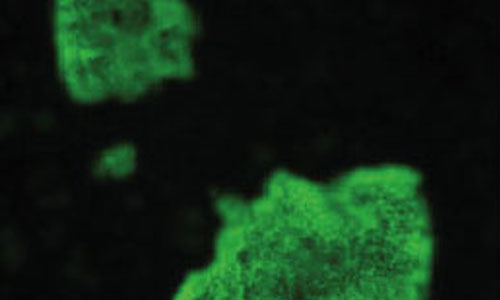

Un ensayo de inmunofluorescencia microfotografía de bartonella hensalae. Cada vez más, se les pide los veterinarios responder a las preguntas relacionadas con las enfermedades potencialmente…